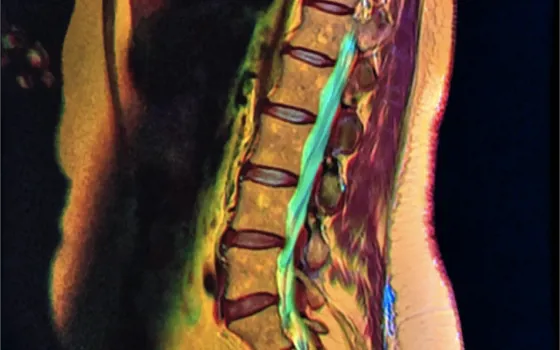

En un estudio publicado recientemente (Herzog, Elgort, Flanders, & Moley, 2017), la misma paciente, una mujer de 63 años, con historia de dolor lumbar y síntomas radiculares L5 en su miembro inferior derecho, visitó 10 centros de imagen diferentes en…